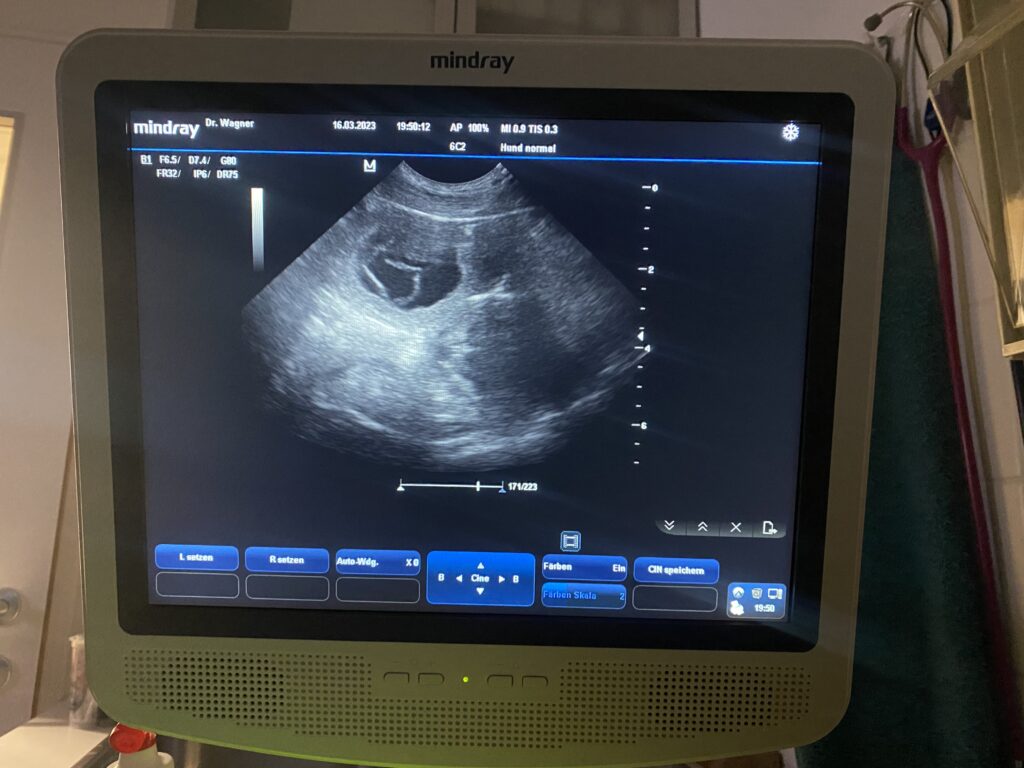

Florence is PREGNANT! The ultrasound confirmed that Florence is pregnant, and we are so excited for our puppies at the end of April.